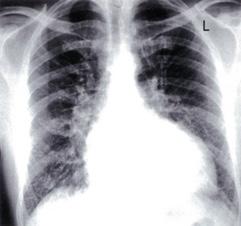

Derrame pericárdico severo da imagen en botellón en la radiografía de tórax. (ENAM EXTRA 2021)

Radiología:

Cardiomegalia

Signos de congestión pulmonar.

Radiografía: cardiomegalia con hipertensión venosa pulmonar